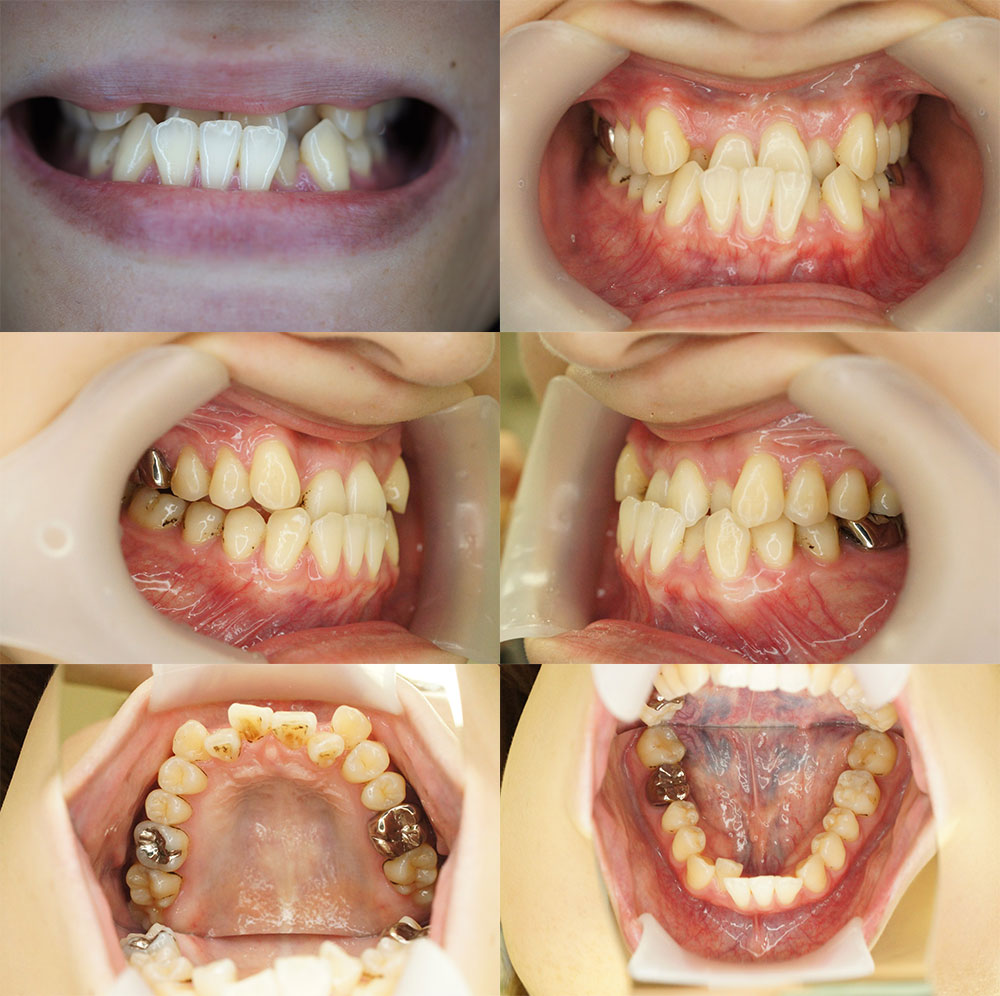

小児矯正の症例1

| 患者様 | 8歳 男の子 | ||

| 主訴 | かみ合わせが上下反対になっているのを治したい | ||

| 治療内容 | 拡大床装置とマウスピース(ムーシールド)による矯正治療をしました。 <初診時> ムーシールド装置を使って舌で上の前歯を押して反対咬合を徐々に治していきました。 下顎の左右C(乳歯の3番目の歯)がかみ合わせに参加していないので歯がとがったままになっています。 上の歯にぶつかっているのでぶつかる部分を削ります。 <1年後> かみ合わせが切端咬合に変わりました。 レントゲン写真から下顎の左右3番の歯(犬歯)のスペースがないことが分かったので、拡大床装置で顎を広げる治療を開始しました。 上下のプレート(拡大床矯正装置)の画像です。【お名前が出てしまうので、加工をお願いします】 上の2番目の歯も顎を広げながら下顎と同様にスペースを作ってゆきます。拡大床装置は補助ワイヤーがある設計になっています。 就寝時のほかに家にいる時間に装着していただいて、保護者様の管理のもと治療をすすめてゆきます。 歯を磨いた後に装着していただいてます。 付けている時間がしっかり確保できるとその分、歯が動きスペースが出来てきます。 <1年6ヶ月後> 上下のかみ合わせがそろってさらに反対咬合が治ったので口角がしっかり上がるのがわかります。 上下の歯のアーチも美しく揃いました。 個人差がありますが上顎が10歳・下顎が12歳ごろまでの成長期となります。 しっかり永久歯が生えるまで定期検診をおすすめしています。 また、永久歯になった後も虫歯にならないためにも定期検診は重要です。 |

| 治療期間 | 1年6ヶ月 | ||

| 通院回数 | 20回 | ||